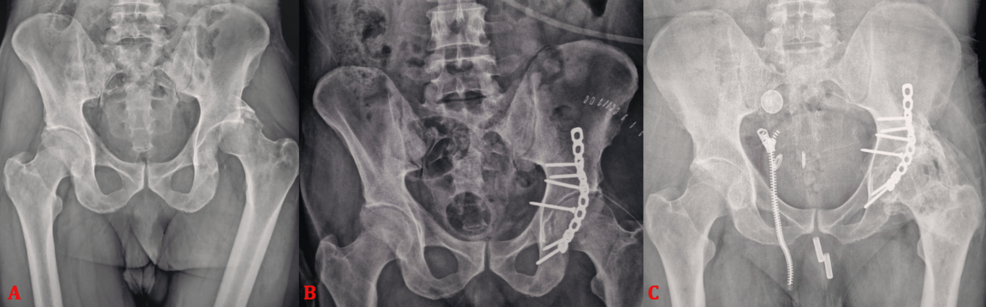

Un estudio reciente publicado en Cureus analiza la complejidad quirúrgica y los posibles errores técnicos en la realización de una artroplastia total de cadera en pacientes con secuelas de fracturas acetabulares. La investigación se basa en una serie de 16 casos, buscando identificar desafíos específicos en este tipo de intervenciones.

El estudio detalla las dificultades encontradas durante la cirugía, incluyendo la necesidad de reconstrucciones complejas del acetábulo y la importancia de una planificación preoperatoria meticulosa. Se destaca la relevancia de considerar la calidad ósea, la presencia de deformidades y la estabilidad de la cadera al seleccionar el tipo de implante y la técnica quirúrgica.